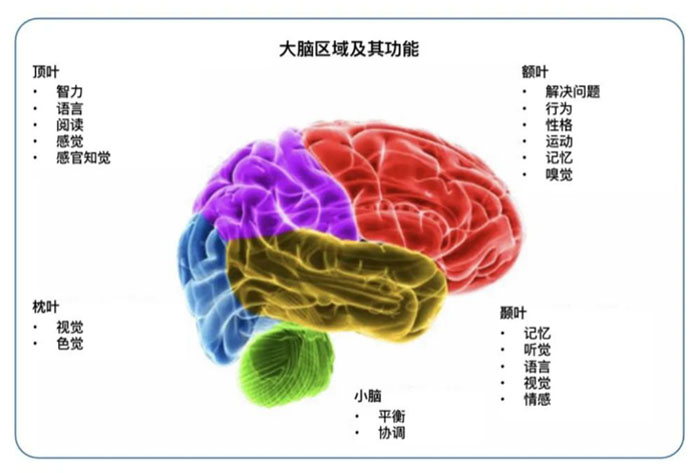

如何及时发现脑胶质瘤?

脑胶质瘤引起的神经系统症状较为广泛。症状可能包括:频繁的头痛伴恶心、惊厥发作、感觉障碍、视力模糊、平衡困难、性格变化等,胶质瘤的症状与肿瘤所在部位的脑功能相关。